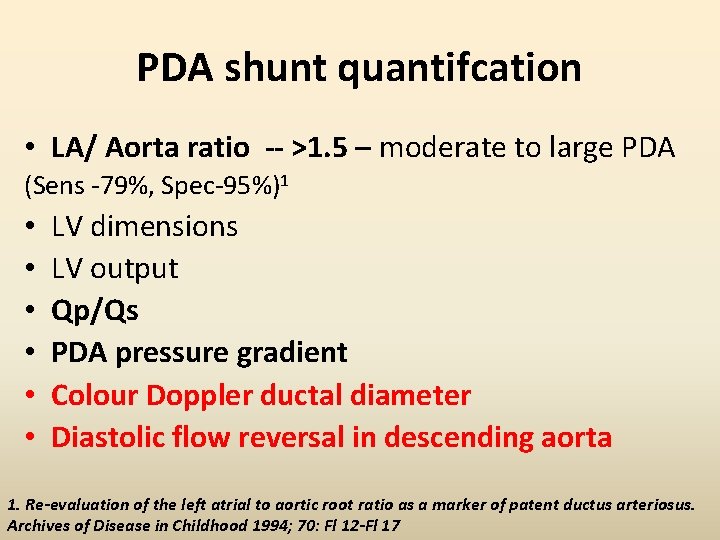

PDA shunt quantifcation • LA/ Aorta ratio -- >1. 5 – moderate to large PDA (Sens -79%, Spec-95%)1 • • • LV dimensions LV output Qp/Qs PDA pressure gradient Colour Doppler ductal diameter Diastolic flow reversal in descending aorta 1. Re-evaluation of the left atrial to aortic root ratio as a marker of patent ductus arteriosus. Archives of Disease in Childhood 1994; 70: Fl 12 -Fl 17